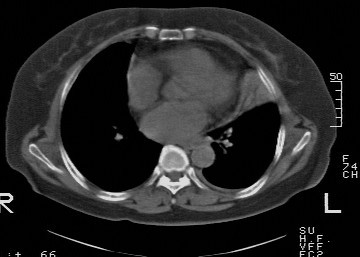

f,74发热咳嗽三天

考虑左肺上叶中央型肺癌并左肺上叶舌段肺不张。

考虑左肺上叶中央型肺癌并左肺上叶舌段肺不张.

左肺上叶舌段肺不张,建议作进一步检查除外中心型肺癌。

左肺上叶舌段肺不张,建议行纤支检查除外中心型肺癌。支持!